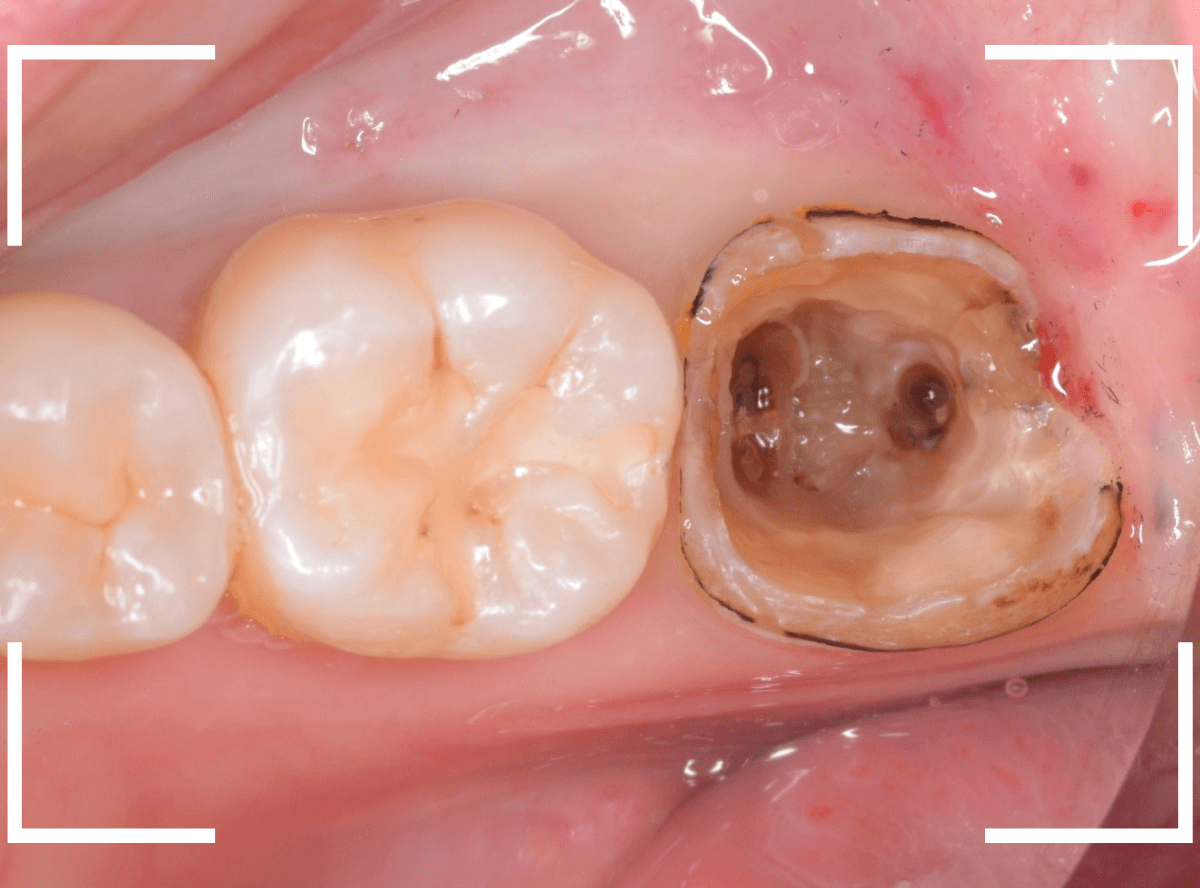

虫歯を全て除去しました。

幸い、あまり多く削る事なく進められたので良かったです。

手前の歯のつめ物も外します。

こちらもお薬が入っていますが、外して中を調べます。

こちらは中も問題なかったです。

奥歯は歯に優しいファイバー・コアで再製し、型取りします。